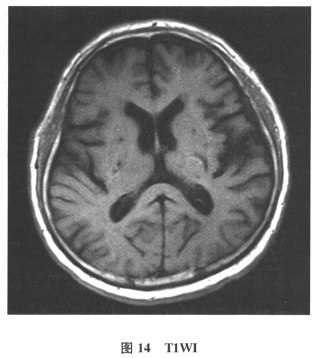

[多选题]患者男,61岁。因“发作性头晕2年,加重伴记忆力下降、走路不稳3月余”就诊。查体:BP140/70mmHg;意识清楚,构音障碍,近期记忆力及远期记忆力